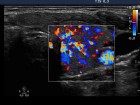

First examination (first row):

Ultrasonography: Both lobes were enlarged, moderately hypoechogenic, inhomogeneous and displayed increased vascularization.

Diagnosis: Graves' hyperthyroidism.